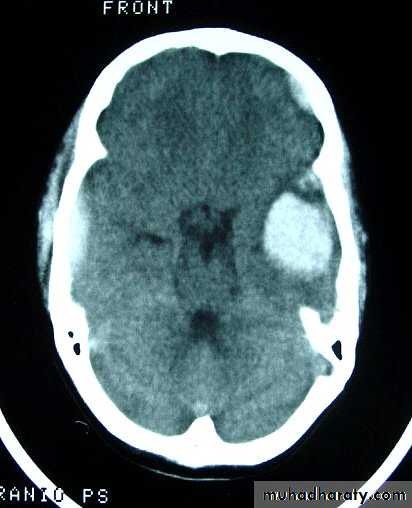

b. Subdural Haematoma

They are the most common intracranial mass lesions resulting from head trauma.They are classified depending on how long they take to present clinically following the injury into:

Acute Subdural Haematoma: less than 3 days

Acute Subdural Haematoma

Usually due to MORE SEVER high velocity trauma and thus associated with a poorer outcome.Source of bleeding (haematoma): include:

Most result from torn bridging veins or focal tears of a cortical artery.

Cortical lacerations or contusions.

Bleeding from tears in the dural venous sinuses.

Clinical Picture: patient will present with a picture similar to that of an extradural haematoma, but there is persistent loss of consciousness with no lucid interval.Ct scan will show a concave hyperdence collection because blood follows the subdural space over the convexity of the brain.

Acute Subdural Haematoma are rapidly evolving lesions and early evacuation via craniotomy is mandatory.